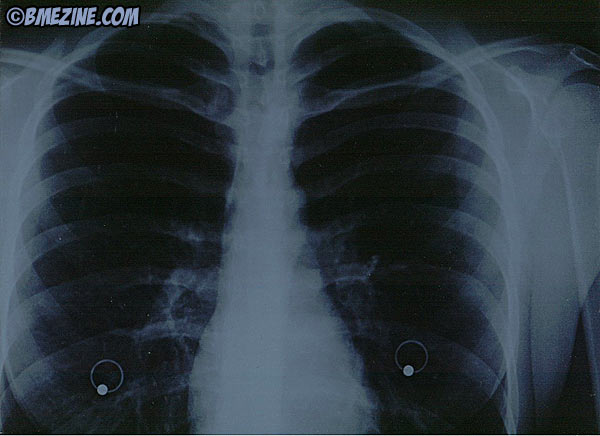

Seguro que cuando vas por la calle te encuentras a algún pavo que va lleno de aretes y te quedas mirándole con cara de ¿cómo es posible que lleve todo el cuerpo agujereado? Pues… si encima ha de ir a hacerse una radiografía… ¿qué pasa?